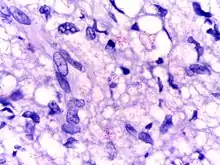

Microphotograph of Mycobacterium leprae taken from a skin lesion. The small brick-red rod-shaped cells appear in clusters. Source: CDC | |

Mycobacterium leprae is an intracellular, pleomorphic, non-sporing, non-motile, acid-fast, pathogenic bacterium.[3] It is an aerobic bacillus (rod-shaped bacterium) with parallel sides and round ends, surrounded by the characteristic waxy coating of mycolic acid unique to mycobacteria. It is Gram-positive by Gram staining, but Mycobacterium leprae was traditionally stained with carbol fuchsin in the Ziehl–Neelsen stain. Because the bacilli are less acid-fast than Mycobacterium tuberculosis (MTB), the Fite-Faraco staining method, which has a lower acid concentration, is used now.[9][10] In size and shape, it closely resembles MTB. The bacteria are found in the granulomatous lesions and are especially numerous in the nodules. This bacteria often occur in large numbers within the lesions of lepromatous leprosy and are usually grouped together as a palisade.[6] By optical microscopy of host cells, Mycobacterium leprae can be found singly or in clumps referred to as "globi", the bacilli can be straight or slightly curved, with a length ranging from 1–8 μm and a diameter of 0.3 μm.[11] The bacteria grow best at 27 to 30 °C, making the skin, nasal mucosa and peripheral nerves primary targets for infection by Mycobacterium leprae.[12]